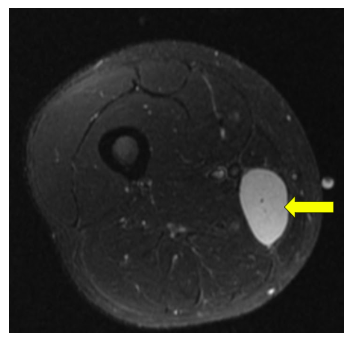

Radiographic imaging is used to help form a diagnosis. These include X-Ray, MRI, CT and Bone Scans.

An example of an MRI is shown.